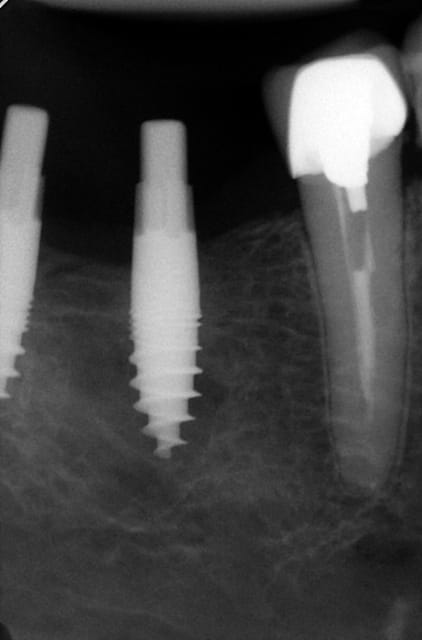

Si je comprends bien on ne peut poser tes implants si on a les dents en place au préalable ...En postérieur c'est léger , les dents étaient absentes lorsque tu as vu ce patient ?

Ned2 tfirxz - Eugenol